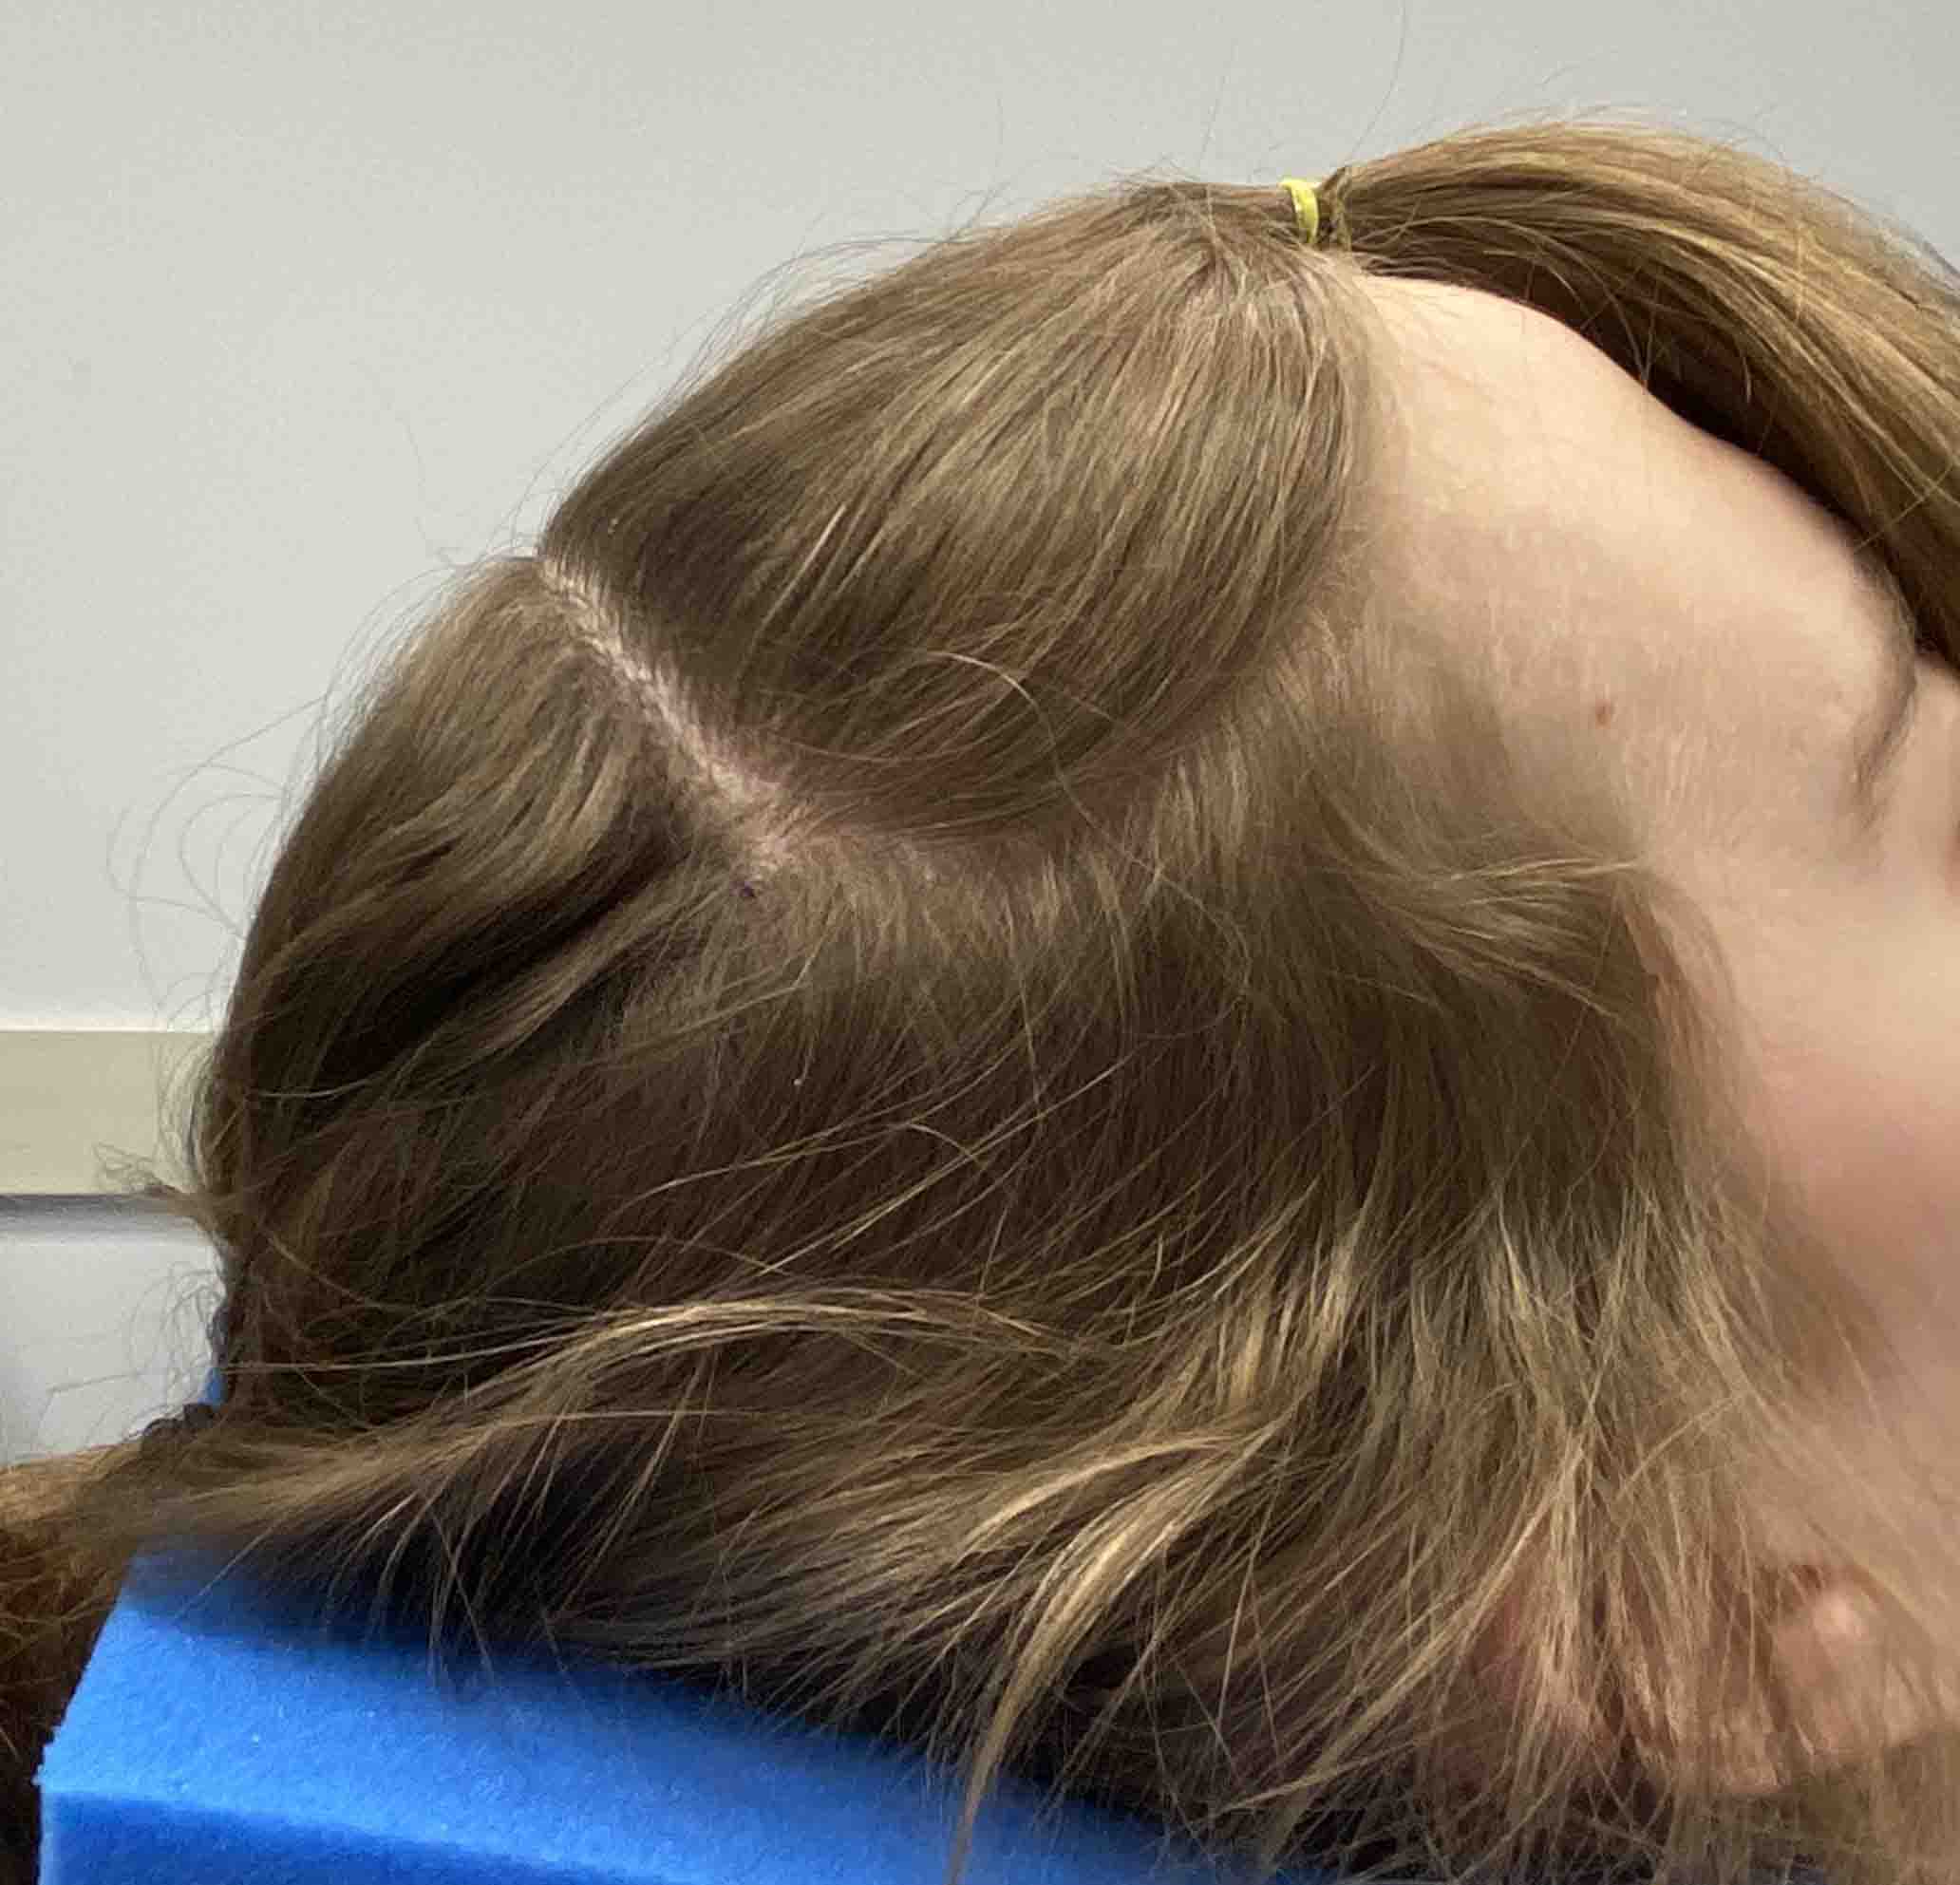

Patient 12

Desire to make her small head taller and wider.

Two stage skull augmentation using a first stage scalp expansion and a second stage custom skull implant for increased head height and shape.